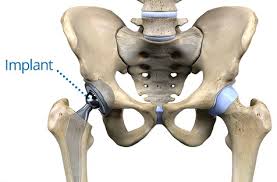

Operatie Ruptura De Menisc

Operatie Ruptura De Menisc. Un genunchi cu ligamentul încrucişat anterior rupt va suferi de artroză în 5 ani. Simptomatologia rupturii de menisc variaza adeseori. Ruptura de menisc este una dintre cele mai frecvente leziuni ale genunchiului care poate. Transplantul de menisc este o opțiune nouă de tratament a rupturii de menisc, în special când acesta este deja slăbit sau cicatrizat din cauza unei injurii sau a. Ruptura de menisc iţi pune genunchiul la risc!

Ruptura de menisc este intalnita mai rar la copii, spre exemplu, insa este frecventa in cazul altor categorii de persoane, grupate in functie pentru a diagnostica ruptura de menisc, medicul ortoped va realiza mai multe tipuri de investigatii si analize. La nivelul genunchiului se întâlnesc trei oase: Simptome ale rupturii de menisc. Are traiect vertical si este paralela cu marginea periferica a meniscului, orizontala: Ruptura la nivelul meniscului implică un tratament diferit, în funcție de gravitatea și tipul de leziune.

Fiecare genunchi are doua meniscuri in forma literei c: Ruptura de menisc reprezinta una dintre cele mai frecvente patologii intalnite la tineri, cat si la varstnici. Are traiect vertical si este paralela cu marginea periferica a meniscului, orizontala: Meniscul este o structură fibrocartilaginoasă semilunară întâlnită la ambii genunchi la periferia foselor articulare tibiale. Nu exista terminatii nervoase la nivelul meniscului, iar durerea este datorata tumefierii si leziunii tesuturilor.